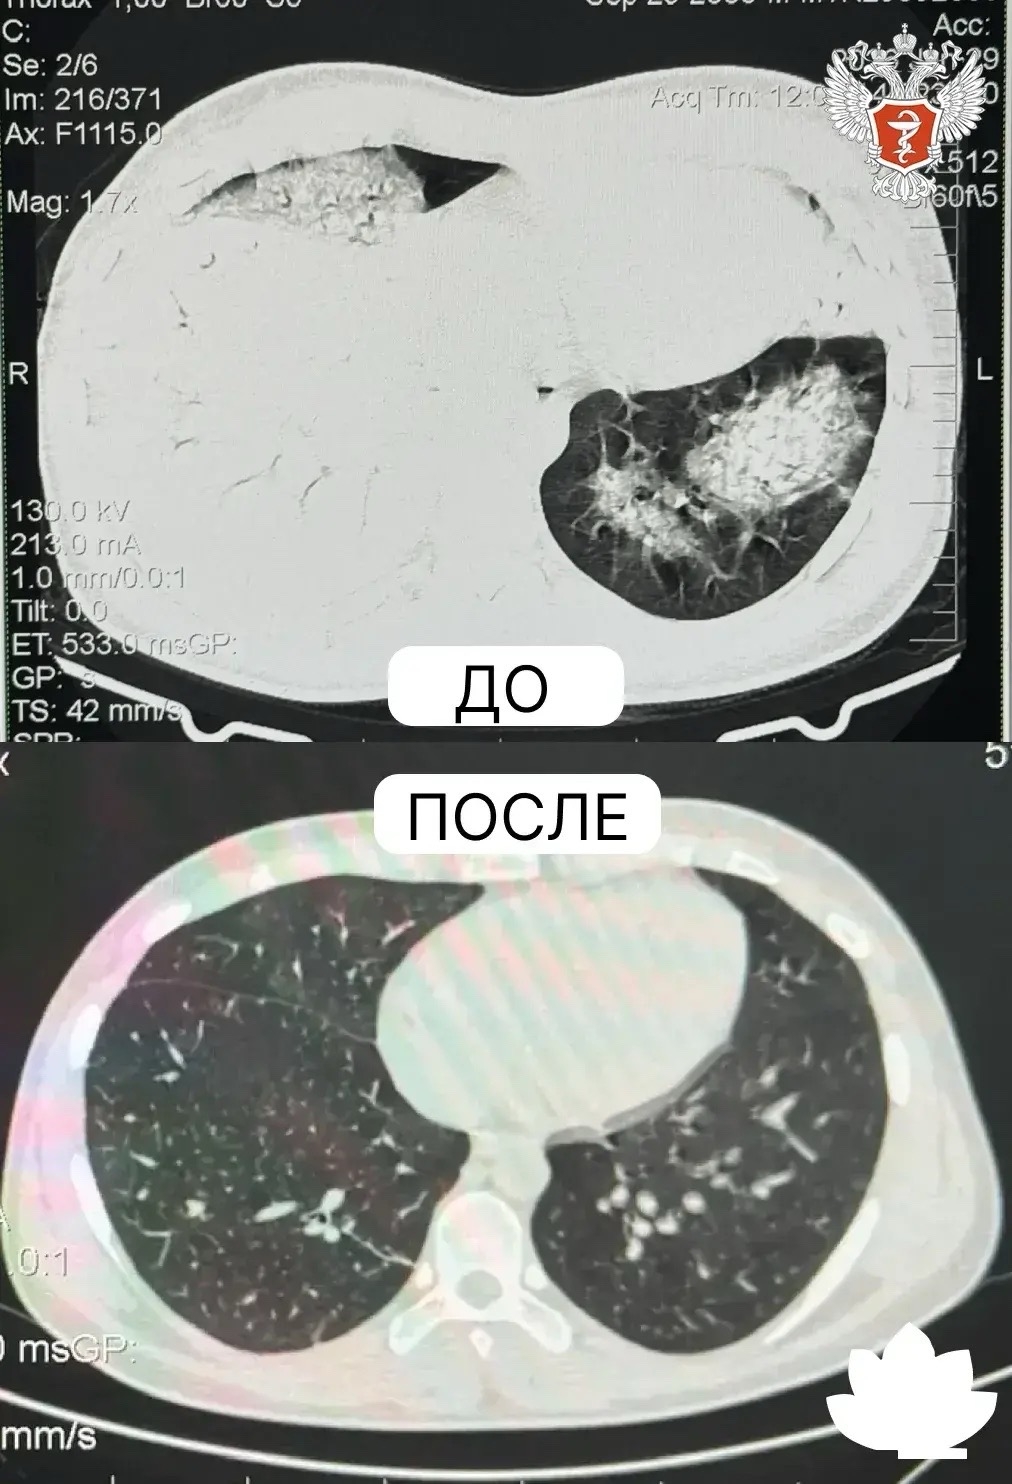

Врачи диагностировали тотальную двустороннюю пневмонию, дыхательную недостаточность и нарушение функций печени. Без своевременной помощи такое состояние опасно критическим кислородным голоданием органов и риском их отказа.

Результаты анализов и компьютерной томографии показали положительную динамику: абсцессы легких значительно уменьшились, некоторые и вовсе закрылись.